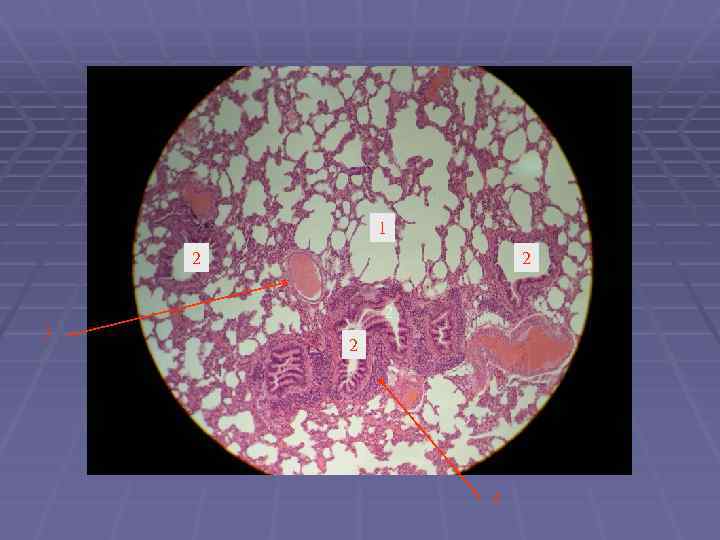

Препарат: Легкое Окраска: гематоксилин-эозин Увеличение: малое альвеолы

1 – бронх среднего калибра 5 – бронх мелкого калибра 6 – респираторный отдел (альвеолы) 8 Бронх среднего калибра: 2 – слизистая оболочка 3 – подслизистая оболочка 4 – фиброзно – хрящева оболочка 7 – мышечный слой слизистой оболочки 8 – железы подслизистой оболочки 9 - хрящевая пластинка 10 - артерия 9 9 6 6 1 9 7 2 8 8 3 9 10 4 5 6

1 – бронх мелкого калибра 2 – терминальная бронхиола 3 – респираторная бронхиола 4 – альвеола 5 - артерия 3 1 4 2 1 5 1 1 4 4